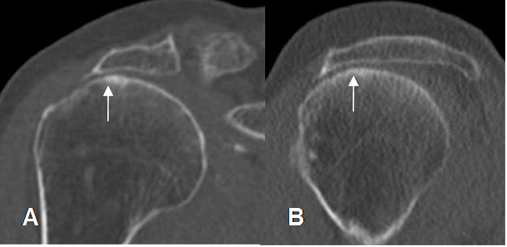

A: TAC reconstrucción coronal y B: TAC reconstrucción sagital. Ruptura del tendón supraespinoso, con pérdida del espacio del arco coracoacromial.

Fig 86. Os acromial.